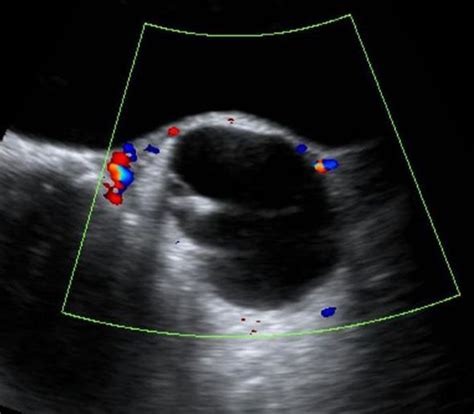

When a physician suspects a dermoid cyst ovary, they will utilize specific diagnostic tools to confirm the presence, size, and location of the mass. Imaging is the gold standard for diagnosis because the specific contents of these cysts—such as fat, calcium (teeth/bone), and fluid—have distinct appearances on scans.

Pelvic Ultrasound The primary tool to visualize the cyst and determine if it is solid or fluid-filled.